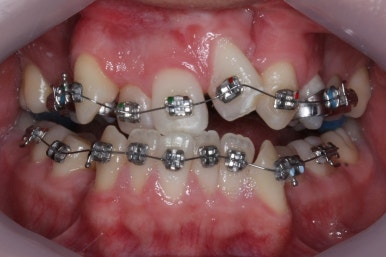

부산구순구개열 키다리아저씨치과에 처음 오셨을 때의 입 안의 모습입니다.

입천장이 갈라져서 어릴 때 봉합 수술을 했기 때문에 그 상처가 굵게 남아있는 것을 볼 수 있습니다. 일반적으로 피부상처도 다른 부위보다 단단하듯이 입천장의 봉합 상처도 매우 단단하게 아물기 때문에 성장에 방해를 주게 됩니다.

가로폭이 매우 좁고 찌그러져 있습니다.

또한 위턱이 앞으로 자라나는 것도 방해해 대부분 앞니가 거꾸로 물리게 됩니다.

또한 가랄져 있던 선에 걸쳐 있는 영구치 일부는 선천결손이 되는 경우가 많습니다.

이번 환자분도 이런 특징을 모두 갖고 계셨습니다.